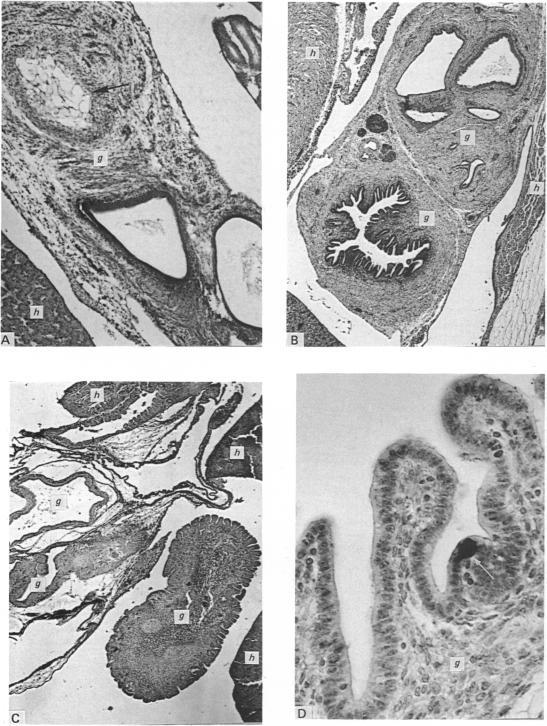

Proceedings of the anatomical society of great britain and ireland, july 1986.

J Anat. 1986 Dec;149:209-48.

17103595

https://pmc.ncbi.nlm.nih.gov/articles/PMC1261653/